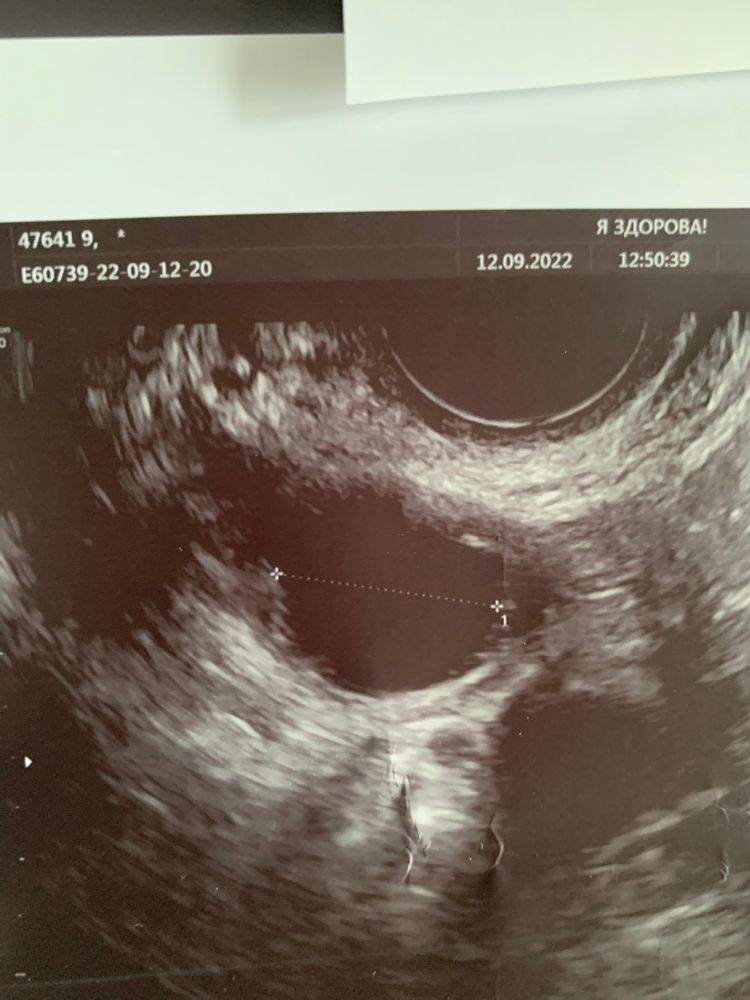

Катерина, 24-26 цикл обычно. Овуляция на 10-12 дц. На узи была в сентябре фолликулометрии. Там был похожий дф, но не такой сплющенный и ставили именно дф на 8 дц. А сейчас более сплющенный)

Такой вот сплющенный)